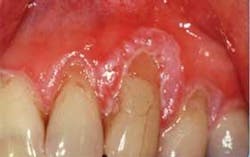

Oral examination: As you begin your intraoral exam, you notice that the gingival tissue is dark pink and appears ulcerated at the margins, especially around tooth Nos. 9–13 (see Figure 1). Rose tells you that this area is of concern to her and that this fact is really why she scheduled the appointment with you today. She is unhappy with the appearance of her teeth, and is worried about the bleeding that she has noticed during the past several months.

As you assess the tissue, you refer to the previous radiographs and digital slides from several years ago. You see a noticeable difference. The tissue today appears bulbous, spongy, ulcerative, and has much more recession than noted previously. As you probe the area, there is spontaneous bleeding. You report your findings to the dentist, and he requests a biopsy of the gingival tissue, referring her to an oral surgeon. Several days later, the pathology report indicates a diagnosis of squamous cell carcinoma of the gingiva.

Distinguishing characteristics: Figure 1 suggests a later stage squamous cell carcinoma of the gingiva. Squamous cell carcinoma of the gingiva may appear very benign in its early stages. It is only after the tissue begins to change appearance and rapidly grow that suspicion usually begins to take place. Intraoral digital photographs are especially important in comparing subtle tissue changes.